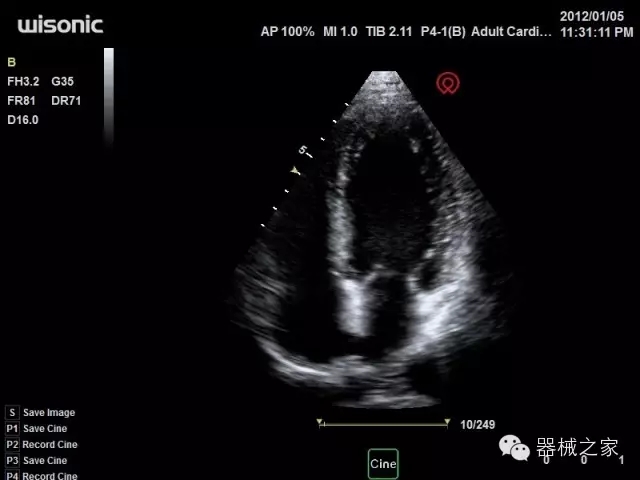

臨床圖片賞析

產(chǎn)品特點(diǎn)

·全球目前唯一一款配備主機(jī)雙探頭接口,整機(jī)重量(含電池)在5公斤以內(nèi)的便攜式彩超;

·獨(dú)有的HoloTM PW 實(shí)時(shí)3取樣門PW成像技術(shù),精確進(jìn)行血管診斷;

·一鍵優(yōu)化B、Color、PW,Auto Doppler自動(dòng)識(shí)別血管位置、偏轉(zhuǎn)角度等,提高工作效率;

·30°超廣角精細(xì)偏轉(zhuǎn)成像技術(shù),更優(yōu)異的頻譜圖像;